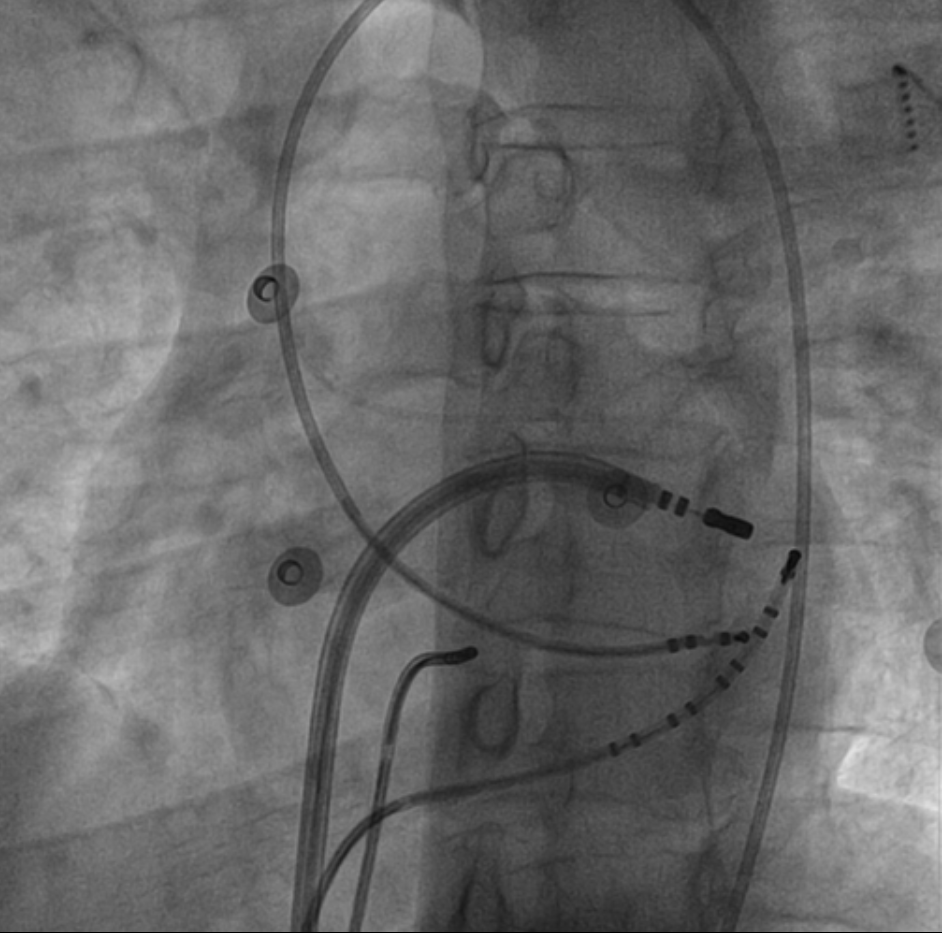

Pacing from LV

lv_catheter.png

Pacing from CS tributary

cs_pacing.jpg

Isthmus block

isthmus_block.jpg